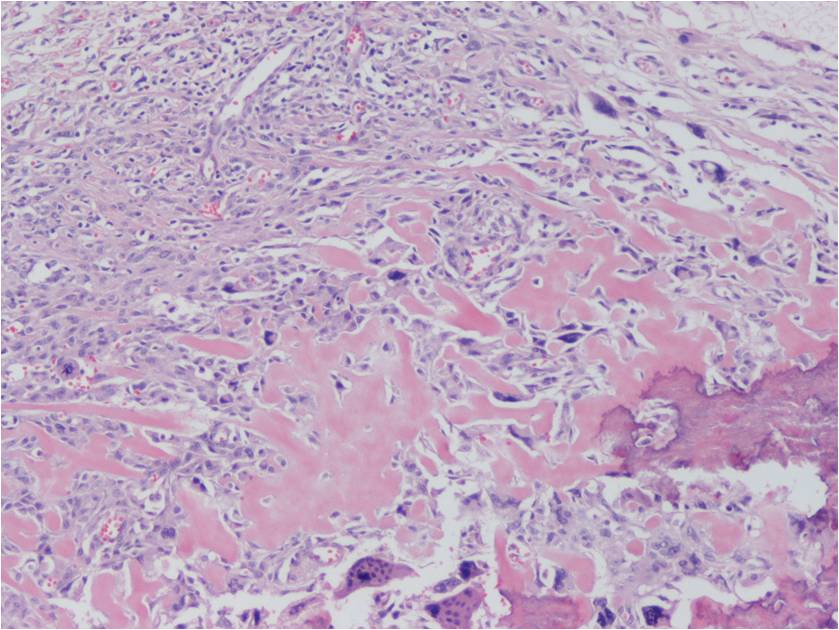

Extraskeletal osteosarcoma is generally a high-grade malignancy, similar to a high grade conventional intraosseous osteosarcoma. Microscopically, tumors usually have an infiltrative margin with occasional satellite nodules; however, on gross inspection they appear well defined. Tumor cells produce a variable amount of osteoid and bone (Fig. 8-10). Necrosis and hemorrhage are common. Five subtypes have been described similar to conventional osteosarcoma of bone: osteoblastic; chondroblastic; fibroblastic; telangiectatic; and small cell.

Fig. 8-10: Microscopic Pathology. Low (Fig. 8), intermediate (Fig. 9) and high (Fig. 10) power magnification H&E slides. Osteoid and bone formation produced by tumor cells, without interposition of cartilage. Tumor cells are crowded, disorganized, pleomorphic and darkly stained. There are mitotic figures.